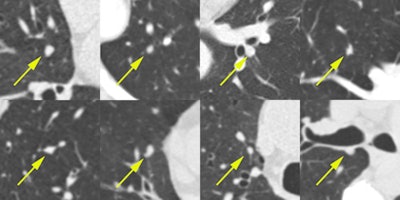

For this, the researchers used the 1,108 false-positive CAD marks from Herakles that had no corresponding mark from any of the LIDC readers. After marks that were obviously not a nodule had been removed by the research team, 269 CAD marks were left for analysis by four new radiologists. Of these, 45 CAD marks were considered to be nodules 3 mm or larger by all four readers. By adding these 45 CAD marks, updated performance of Herakles at its system operating point would reach 83% sensitivity at a rate of three false-positive detections per scan.

The authors offer several reasons as to why these nodules may have been missed the first time: the original LIDC readers only inspected transverse sections, according to the study. Furthermore, the majority of the missed nodules shared characteristics including subtle conspicuity, small size (less than 6 mm) and attachment to pleura or vasculature.